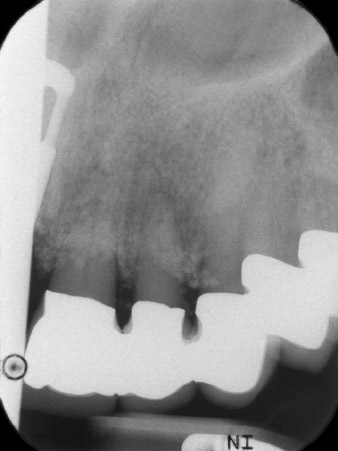

La radio a révélé une perte osseuse horizontale autour des dents 21 et 22 (Fig. 1). Lorsque la structure de couronne a été retirée, ces dents ont involontairement été extraites en même temps.

Une fois la cicatrisation primaire obtenue, les tissus mous ont été formés à l'aide du bridge doublé à la base. Deux mois plus tard, la zone a été exposée au moyen d'une incision de la crête alvéolaire légèrement orientée côté palatin (Fig 2). Les dimensions de l'os alvéolaire se sont avérées suffisantes en position 22. Les Figures 2 et 4 illustrent la préparation du lit implantaire, le taraudage et la pose de l'implant à l'aide de l'Implantmed.